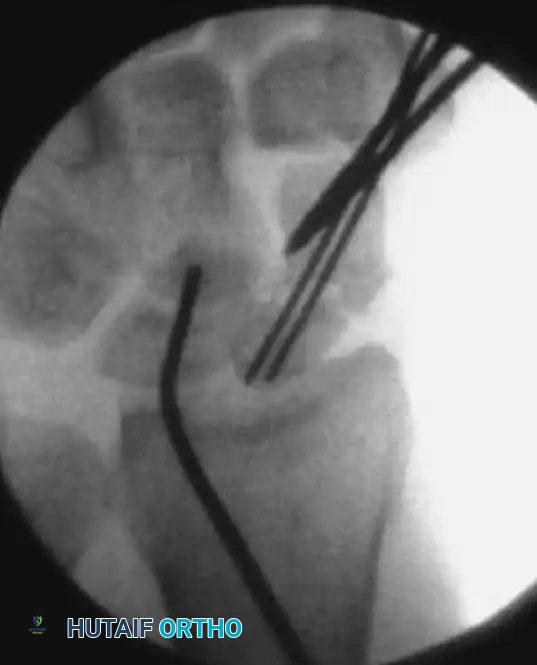

1. Fluoroscopic Targeting and The "Ring Sign"

The cornerstone of the Slade percutaneous dorsal approach is achieving the correct fluoroscopic view to target the central axis of the scaphoid.

• Targeting the Axis: Locate the central axis of the scaphoid on a standard posteroanterior (PA) view of the reduced scaphoid.

• Achieving the Ring Sign: Gently pronate and flex the patient's wrist. Because the scaphoid sits obliquely, flexing and pronating the wrist aligns the proximal and distal poles coaxially with the fluoroscopy beam.

• When perfectly aligned, the scaphoid will project a cortical "ring" appearance on the fluoroscopic monitor. The exact center of this "ring" represents the central axis of the scaphoid—the optimal starting point for the guidewire.

Fluoroscopic Targeting A

Fluoroscopic Targeting B

Fluoroscopic Targeting C

FIGURE: Percutaneous fixation of scaphoid fracture. (A) Central axis of scaphoid located on PA view. (B) Wrist pronated until poles align. (C) Wrist flexed until the scaphoid demonstrates the classic "ring" appearance, indicating coaxial alignment.